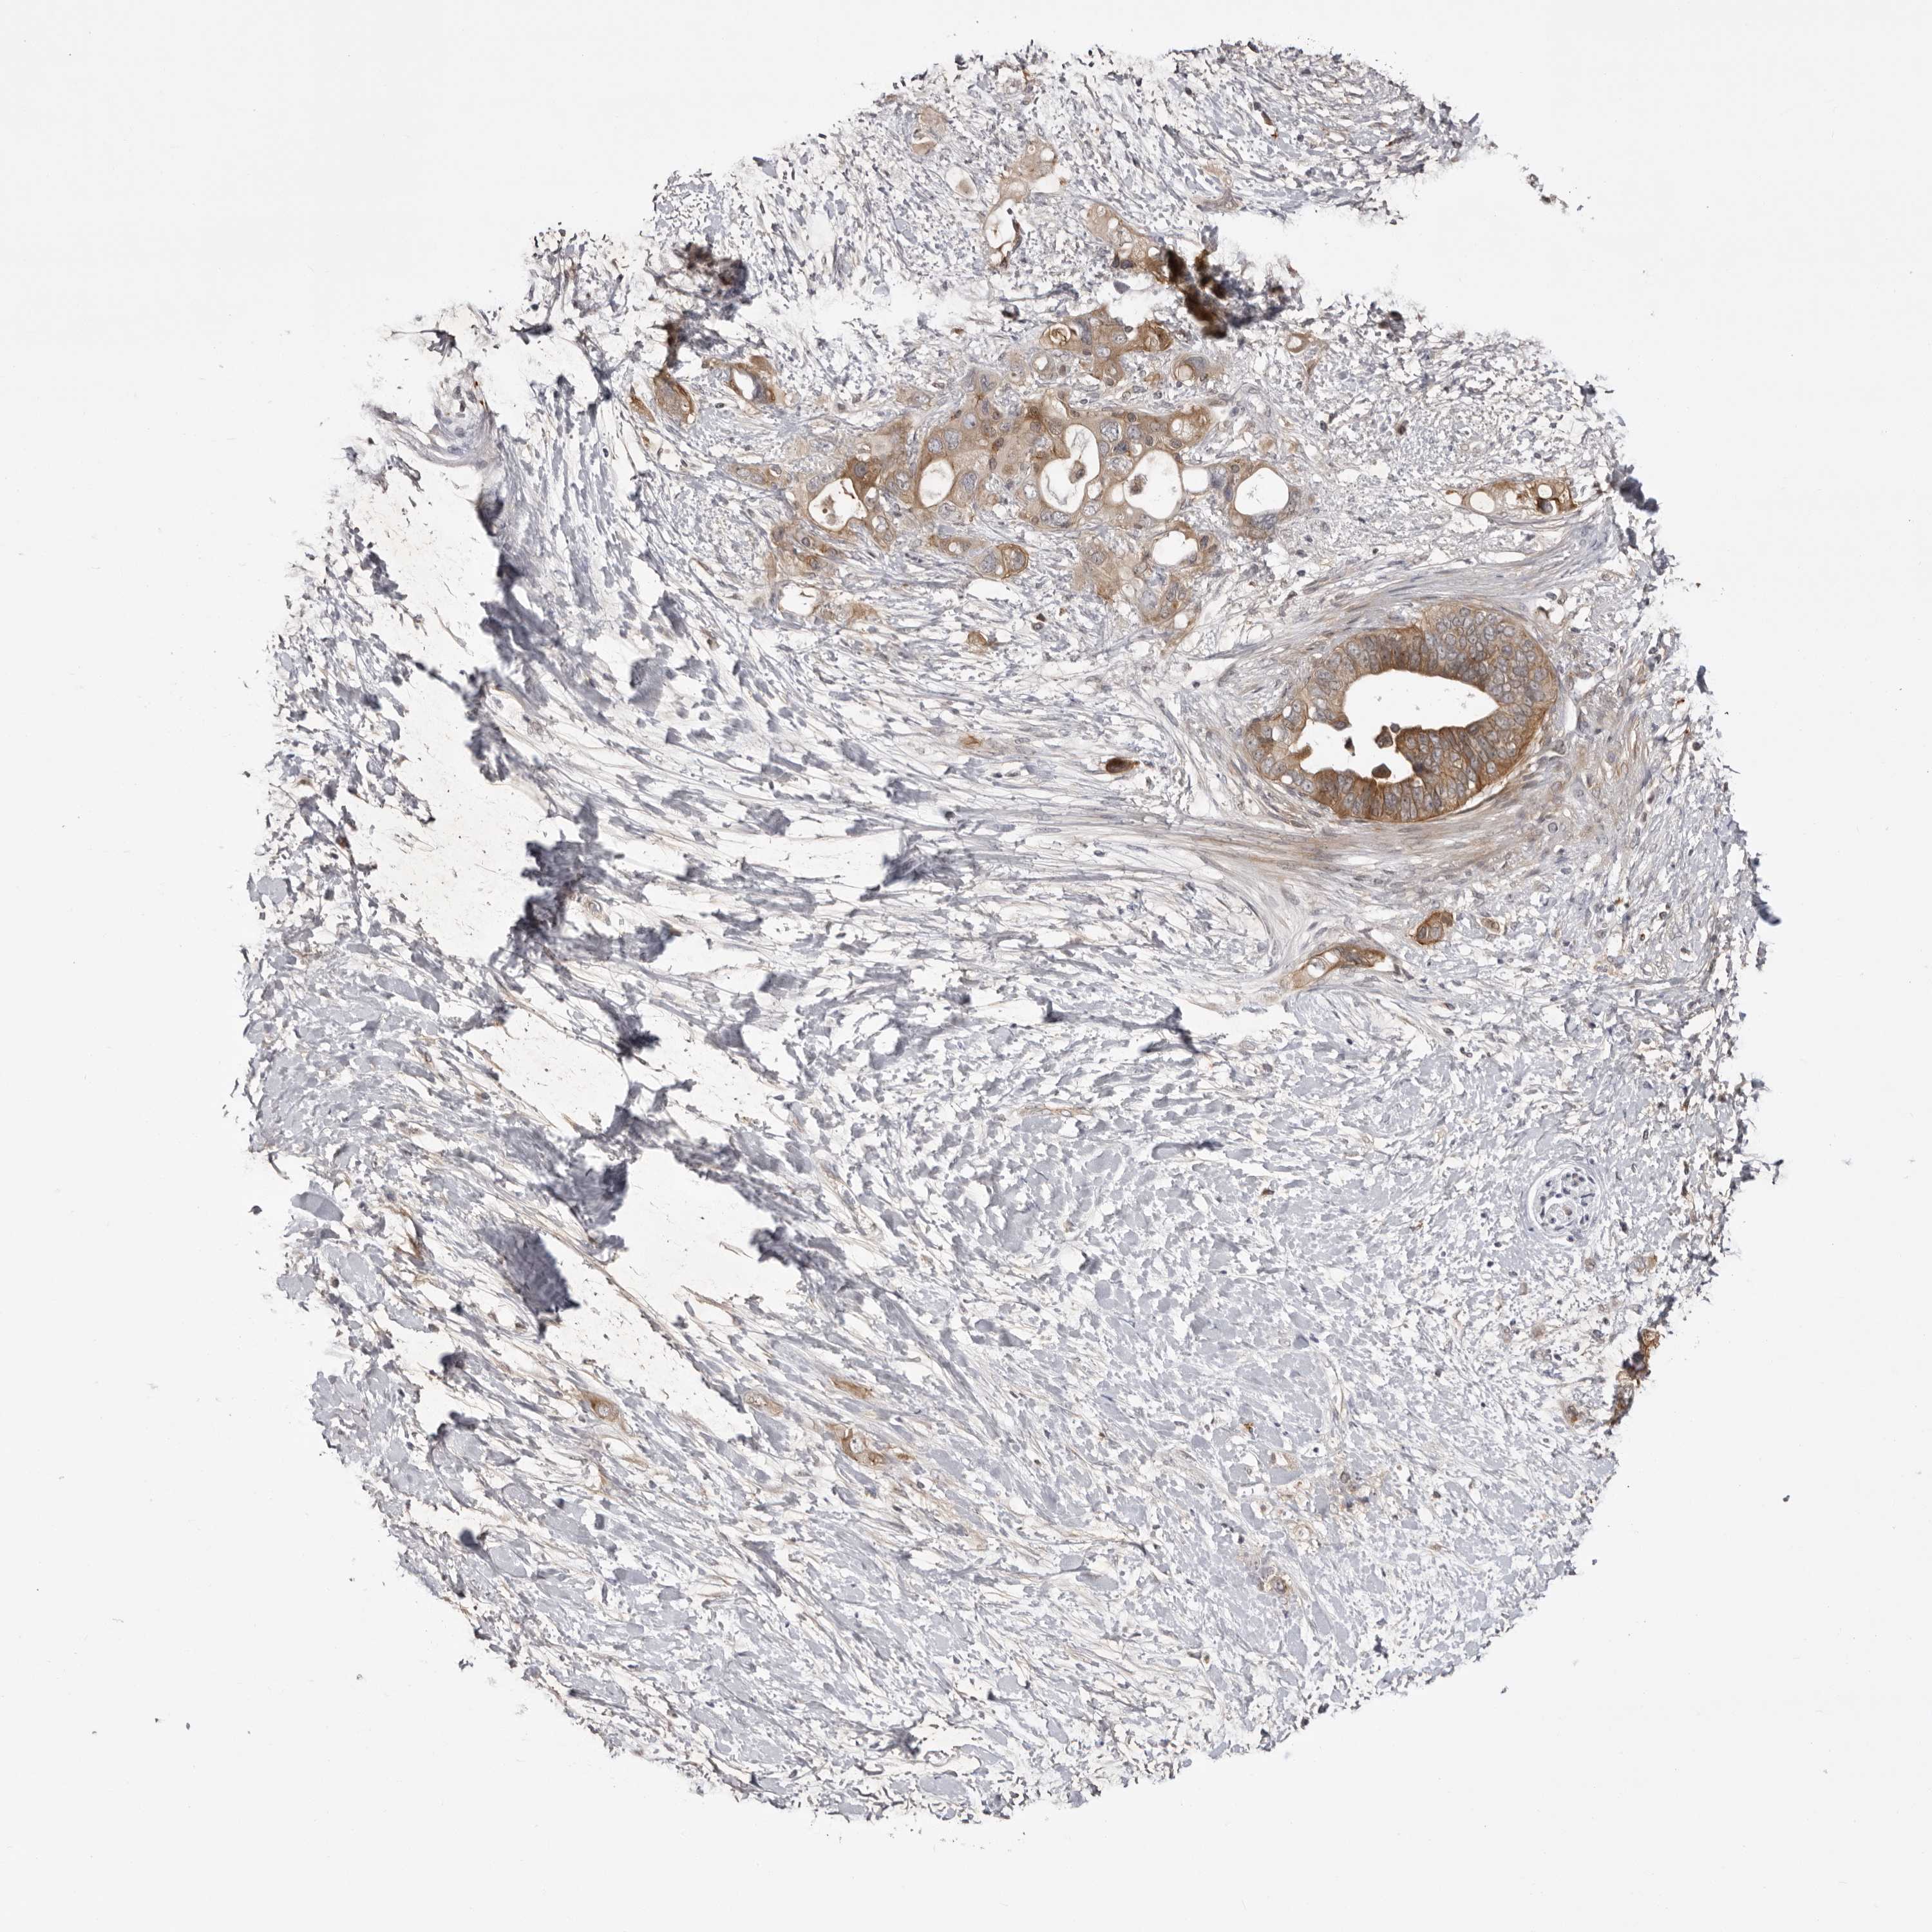

PANCREATIC CANCER - Protein expressioni

A mouse-over function shows sample information and annotation data. Click on an image to view it in a full screen mode. Samples can be filtered based on level of antibody staining by selecting one or several of the following categories: high, medium, low and not detected. The assay and annotation is described here.

Note that samples used for immunohistochemistry by the Human Protein Atlas do not correspond to samples in the TCGA dataset.

Antibody stainingi

Antibody staining in the annotated cell types in the current human tissue is reported as not detected, low, medium, or high, based on conventional immunohistochemistry profiling in selected tissues. This score is based on the combination of the staining intensity and fraction of stained cells.

Each image is clickable and will lead to virtual microscopy that enables deeper exploration of all samples and also displays staining intensity scores, fraction scores and subcellular localization as well as patient and tissue information for each sample.

Antibody HPA023389

Antibody HPA027762

Staining

High

Medium

Low

Not detected

Intensity

Strong

Moderate

Weak

Negative

Quantity

>75%

75%-25%

<25%

None

Location

Nuclear

Cytoplasmic/membranous

Cytoplasmic/membranous,nuclear

Adenocarcinoma, NOS